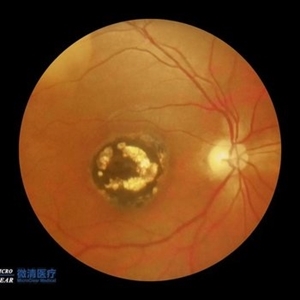

Childhood Acquired Ocular Toxoplasmosis

Childhood Acquired Ocular Toxoplasmosis

Sep 13 2023 by Deepak Bhojwani, MS

Fundus image of a 16 year old boy diaagnosed with Childhood Acquired Ocular Toxoplasmosis since the age of 10 years showing the classic toxo chorioretinitis scar on the posterior pole complicated by Choroidal neovascularisation over the macula. OCT documenting complete foveal atrophy.

Photographer: DR DEEPAK BHOJWANI

Imaging device: OPTICAL COHEERENCE TOMOGRAPHY

Condition/keywords: choroidal neovascularization (CNV), toxo chorioretinitis